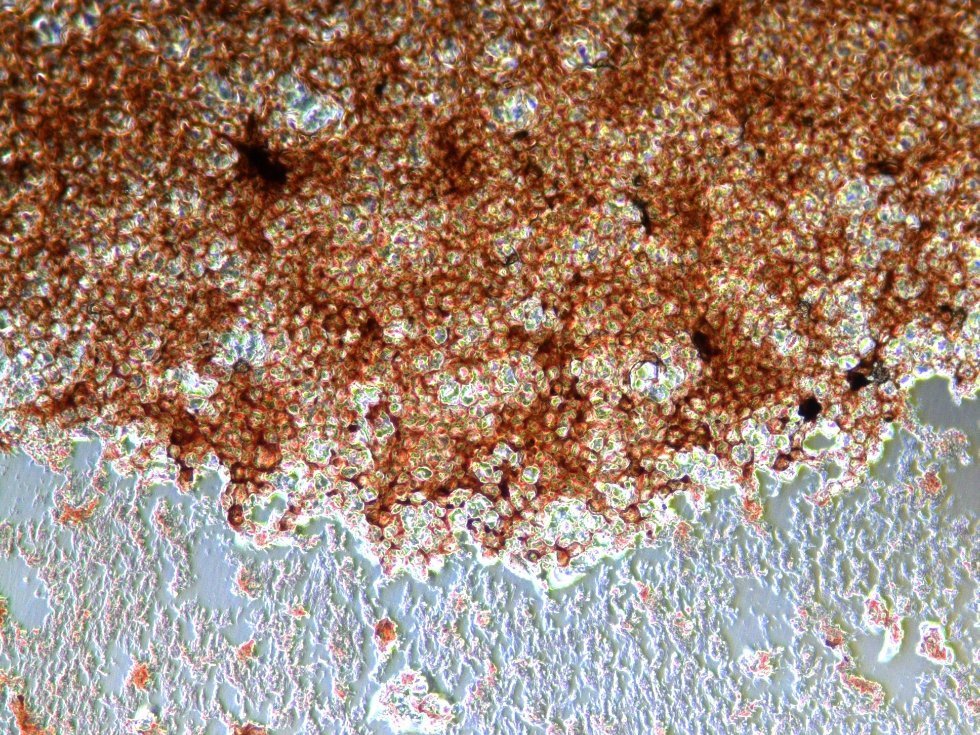

- We attach nanoparticles to the surface of membranes and they don`t penetrate into cells. In this way we almost avoid the possibility of negative impact on enzymes and genetic apparatus. As result magnetic “cells-cyborgs” are able to grow and divide as effectively as intact (source cells). In the framework of the Russian Foundation for Basic Research project we synthesize particles so they are able to be attached to cells. Consequently cells covered with nano particles act like microscopic magnets and they can be concentrated and kept in space with the help of an ordinary constant magnet. Today we use such living structures with additional features for producing artificial multi-layered clusters – tissue prototypes.

- The first part of the project is almost ready. We synthesized nano particles and determined their peculiar features. We made magnetic modification of isolated human cells. We chose model cells magnetized by nano particles. We defined experiment conditions for their optimal magnetization. Besides, we conducted researches on an assessment of toxicity of magnetic nanoparticles in relation to cells and found out that magnetic modification did not produce negative impact on their activity.